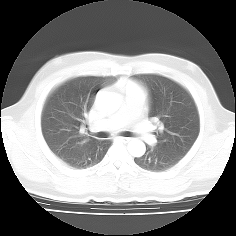

MPR表示について

CTやMRIなどの医療機器によって生成されたスライスシリーズ画像を表示する場合、MPR(多断面再構成)表示法は、非常に有効な読影方法であり、特に任意角度の斜断面画像の再構成(Oblique)表示法は、臨床診断に非常に有用かつ重要な読影手法となっています。

ImageClarityのMPR表示機能は、エンジンレベルで実現したもので、任意空間原点と任意3D方向の断面を表示することが可能になっており、補正表示をしながら実用レベルの高速表示を実現し、3D処理開発キットとしても非常に利用しやすいAPIを提供しています。 MPR以外に、任意サイズのMIP(最大値投影)表示法もサポートしています。

MPR/MIP表示